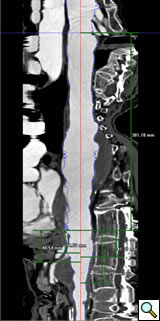

The branched TAAA stentgrafts are a modular system based on the Zenith stentgraft (Cook Inc, Bloomington, Indiana). The main body component is custom designed straight or tapered device with reinforced fenestrations or directional helical branches precisely constructed to correlate with the patients target vessels (Figure 1). Reinforced fenestrations are mated to balloon expandable covered stents (Jomed, Abbott Labs, Abbott Park, Illinois) and the directional branches are mated to self-expanding covered stents (Fluency, Bard, Inc, Tempe, Arizona).

Planning